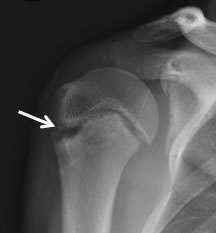

Common Shoulder Injuries With Throwing - DMC

Common Shoulder Injuries with Throwing Written by Suzanne Schmidt, MPT, CSCS For the Rehabilitation Institute of Michigan The shoulder joint is complex and prone to injury because it allows ... Get Document